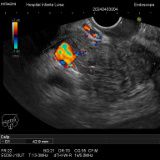

Enfermedades relacionadas con el páncreas

-

Pancreatitis aguda

Pancreatitis crónica

Cáncer de páncreas

Cribado familiar de cáncer de páncreas

Lesiones quísticas pancreáticas